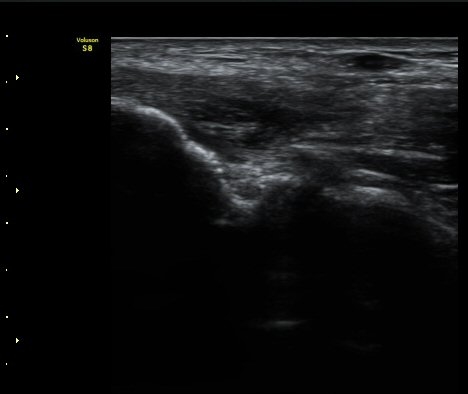

¼Ò½Ç ¹× Àü¹ÝÀûÀÎ Àú¿¡ÄÚ ºÎÁ¾ÀÌ °üÂûµÈ´Ù(±×¸² 1, 2, 3). ±¼°î°Ç ÀϺδ Á¤»óÀûÀÎ °í¿¡ÄÚ

¼¶À¯ ¾ç»óÀ¸·Î °üÂûµÈ´Ù(±×¸² 4). ÈûÁ٠Ⱦ´Ü¸é °Ë»ç¿¡¼­µµ °Ç³» ¿¬°á¼º ¼Ò½Ç°ú Àú¿¡ÄÚ

º¯È­°¡ °üÂûµÈ´Ù(±×¸² 5).  ÃÊÀ½ÆÄÀ¯µµÇÏ ÁÖ»ç ½Ã ÁÖ»ç¾×ÀÌ °Ç³»¿¡¼­ ÀÚÀ¯·Ó°Ô ÆÛÁ®¼­

°ÇÀÇ ½ÉÇÑ ÆÄ¿­À» º¸¿©ÁØ´Ù(÷ºÎ ÆÄÀÏ µ¿¿µ»ó 1).